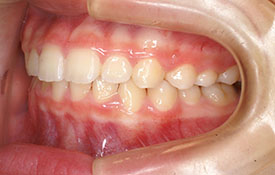

インビザラインの治療例:CASE-2

| プロフィール | 15歳 男性 |

| 所見 | アメリカから転院されて来られた方です。 インビザラインで上下顎の矯正治療を開始し下顎はアメリカで終了しており、上顎のみ治療の後期を担当しました。 アイライナーの装着は、1日平均22時間ほどでした。 |